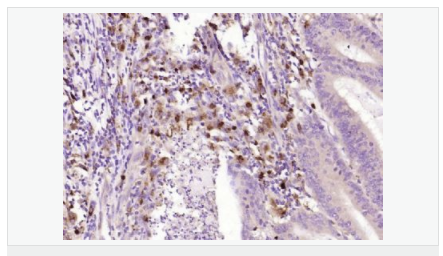

| 產品應用 | WB=1:500-2000 ELISA=1:5000-10000 IHC-P=1:100-500 IHC-F=1:100-500 ICC=1:100-500 IF=1:100-500 (石蠟切片需做抗原修復) not yet tested in other applications. optimal dilutions/concentrations should be determined by the end user. |